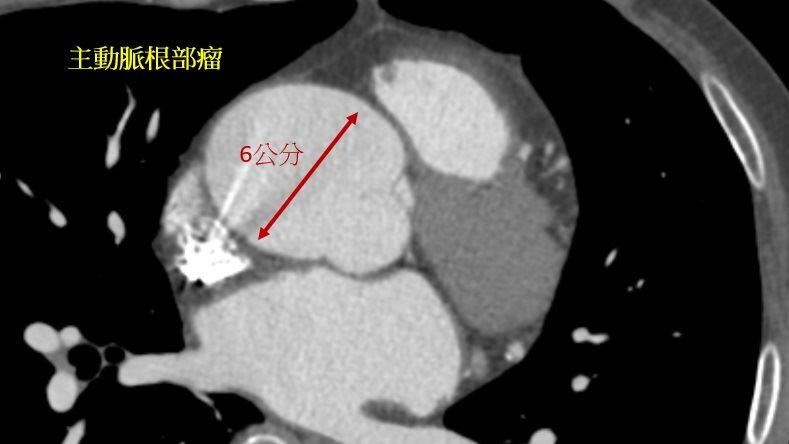

▼▲鍾女士因為大達將近5.5公分的主動脈瘤,導致主動脈瓣逆流。(圖/台北慈濟醫院提供)

長期抽菸的53歲鍾女士素來沒有心臟疾病,但日前在全身檢查中發現心臟主動脈根部居然有顆大達5.3公分的主動脈瘤,於是來到台北慈濟醫院心臟血管外科楊凱文醫師的診間。進一步檢查後,發現鍾女士除了有主動脈瘤外,還伴隨主動脈瓣逆流的問題,於是楊凱文醫師替她施行主動脈根部瓣膜保留置換術,免除主動脈瘤不定時破裂的死亡風險外,未來鍾女士也不用煩惱心臟因長時間逆流而衰竭的可能。

楊凱文醫師說明:「根部的主動脈瘤因為鄰近主動脈瓣,當主動脈根部擴大的時候,原本緊密貼合的瓣膜葉片因為形狀改變,無法緊密貼合,就會導致逆流。過去的研究報告指出大約50-80%的主動脈根部瘤患者會有某種程度的主動脈瓣逆流。」產生主動脈瘤的原因包含動脈粥狀硬化、高血壓、基因遺傳、先天性雙葉主動脈瓣等等,可是無論是主動脈瘤或是重度以下的主動脈瓣逆流病人大多一開始都不會有明顯症狀,而臨床上則是建議主動脈瘤要是大到5.5公分就要進行手術,在特定的病患 (包括馬凡氏症候群及其他遺傳性主動脈病變,或者本身就因為主動脈瓣膜病變要接受心臟手術的病患) 甚至在4.5公分便可建議接受手術。